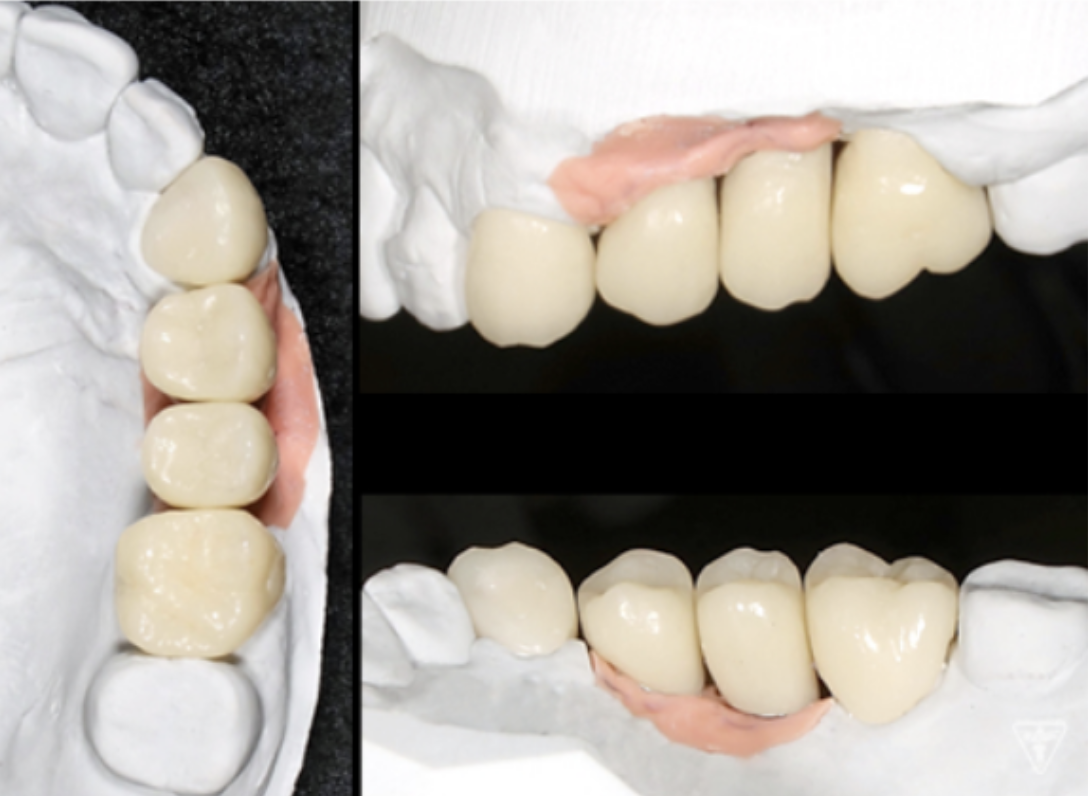

最終補綴物装着時

咬合調整

粉砕効率の高い小さな点による均衝接触をつくります。

咬合様式は、ミューチャリープロテクトオクルージョンを付与しました。